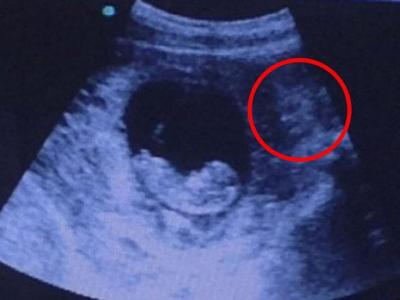

胎儿超声波图现魔鬼脸令人毛骨悚然

不少人留意到超声波图中的诡异“脸孔 超声波图右方的阴影似足一张脸孔 胎儿...